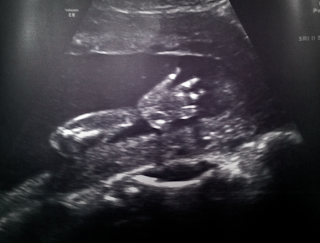

![]() |

| Love you already, baby Goudie... |